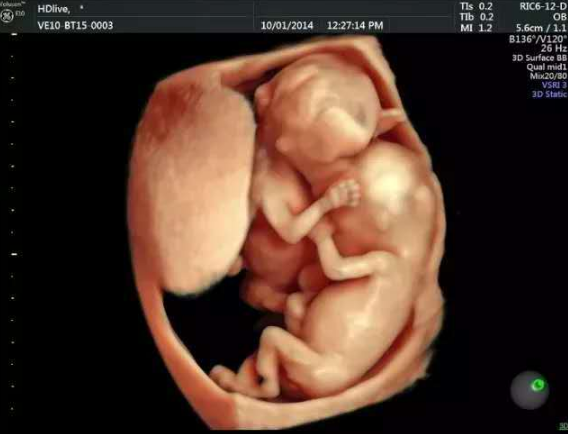

四维彩超是在怀孕24周左右做的,可以筛查胎儿颜面畸形、内脏畸形、四肢畸形等,而她现在是怀孕四个月,也就是怀孕16-18周了,我让她提前咨询医生,预约四维检查了。